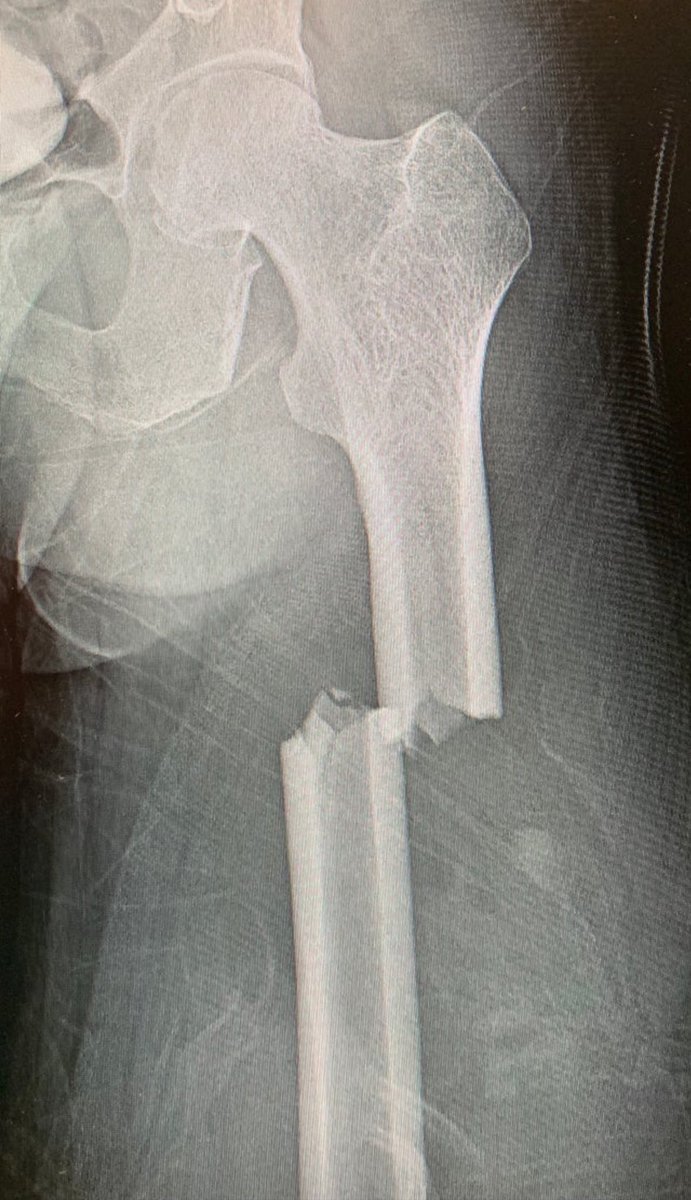

A Boy Ate 150 Chewable Vitamins For Breakfast And This Is What Happened To His Bones Youtube

A Boy Ate 150 Chewable Vitamins For Breakfast And This Is What Happened To His Bones Youtube from www.youtube.com